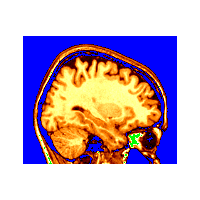

Example 8: Superimposing PET on MRI

This example shows all regions of PET activation above a certain value on top of an MR image. This is accomplished by putting the -gray MR colour coding on the command line, followed by -under transparent, and finally the -spectral colouring of the PET volume.

~david/public_bin/make_slice /data/icbm/mri1/new_icbm/subjects/00100/final/mni_icbm_00100_t1_final.mnc slice.obj x w -30 2 2

~david/public_bin/ray_trace -output ex8.rgb -nolight -gray 80000 450000 /data/icbm/mri1/new_icbm/subjects/00100/final/mni_icbm_00100_t1_final.mnc 0 1 -under transparent -spectral 40 60 /avgbrain/brain/images/mni_demo_cbf_normal_pet_tal.mnc.gz 0 1 slice.obj -size 200 200 -bg white -crop

Example 9: Superimposing PET on MRI with Transparency

The last argument of the colouring coding argument indicates the opacity of the volume colours. By changing the argument: -spectral 40 60 /avgbrain/brain/images/mni_demo_cbf_normal_pet_tal.mnc.gz 0 1 to -spectral 40 60 /avgbrain/brain/images/mni_demo_cbf_normal_pet_tal.mnc.gz 0 .4 , the PET image shows a little of the underlying MR image.

~david/public_bin/ray_trace -output ex8.rgb -nolight -gray 80000 450000 /data/icbm/mri1/new_icbm/subjects/00100/final/mni_icbm_00100_t1_final.mnc 0 1 -under transparent -spectral 40 60 /avgbrain/brain/images/mni_demo_cbf_normal_pet_tal.mnc.gz 0 .4 slice.obj -size 200 200 -bg white -crop